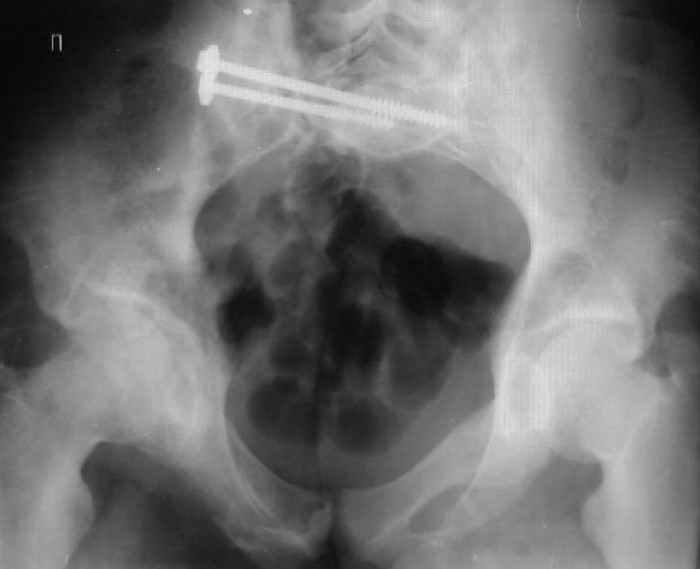

Уважаемые коллеги! Хотел-бы обсудить варианты лечения больной с застарелым переломом таза. Возраст 40 лет. Травма 11 месяцев назад. Главный травматолог Камчатского Военно-морского госпиталя Юрий Алексеевич Булахтин

У больного судя по всему вертикальная деформация таза. А каковы основные жалобы пациента и какие у него функциональные требования?

Мы, как правило, в подобных случаях проводим оперативное лечение в несколько этапов. Первым устраняем деформацию при помощи АВФ (кольцевой конструкции с фиксацией задних отделов), вторым- выполняем введение илиосакралых винтов, накостный остеосинтез передних отделов.

Для информации к размышлению о возможности исправления имеющейся деформации предлагаю похожий случай.